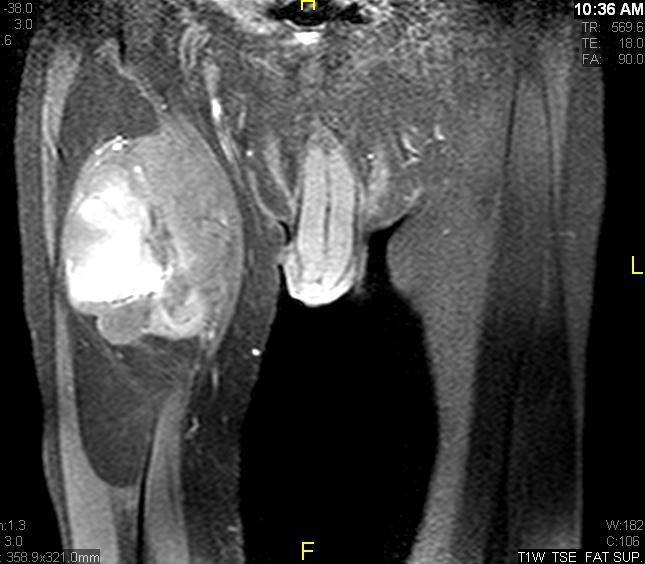

Fig. 7 & 8 Magnetic Resonance Image shows a large heterogeneous mass in the right thigh with low intensity signal on Axial (Fig. 7) and Coronal (Fig. 8) T1-weighted images admixed with high signal areas. The high signal areas represent low grade fatty tissue and low signal the dedifferentiated areas. Higher intensity signal is visible compatible with hemorrhage or necrotic tissue.

Fig. 9 Coronal fat suppressed T1-weigthed MR image demonstrates a large heterogeneous mass in the anterior compartment of the thigh with some areas suppressed corresponding with fatty areas within the tumor. Central hyper enhanced areas compatible with hemorrhage or necrosis.

Fig. 11 – 13 Axial (Fig. 11), Coronal (Fig. 12) and Sagital (Fig. 13) contrasted T1-weighted MR images show a large heterogeneous mass with central and peripheral

enhancement. Multiple thick trabeculations. Central low signal intensity image is compatible with necrosis and hemorrhage.